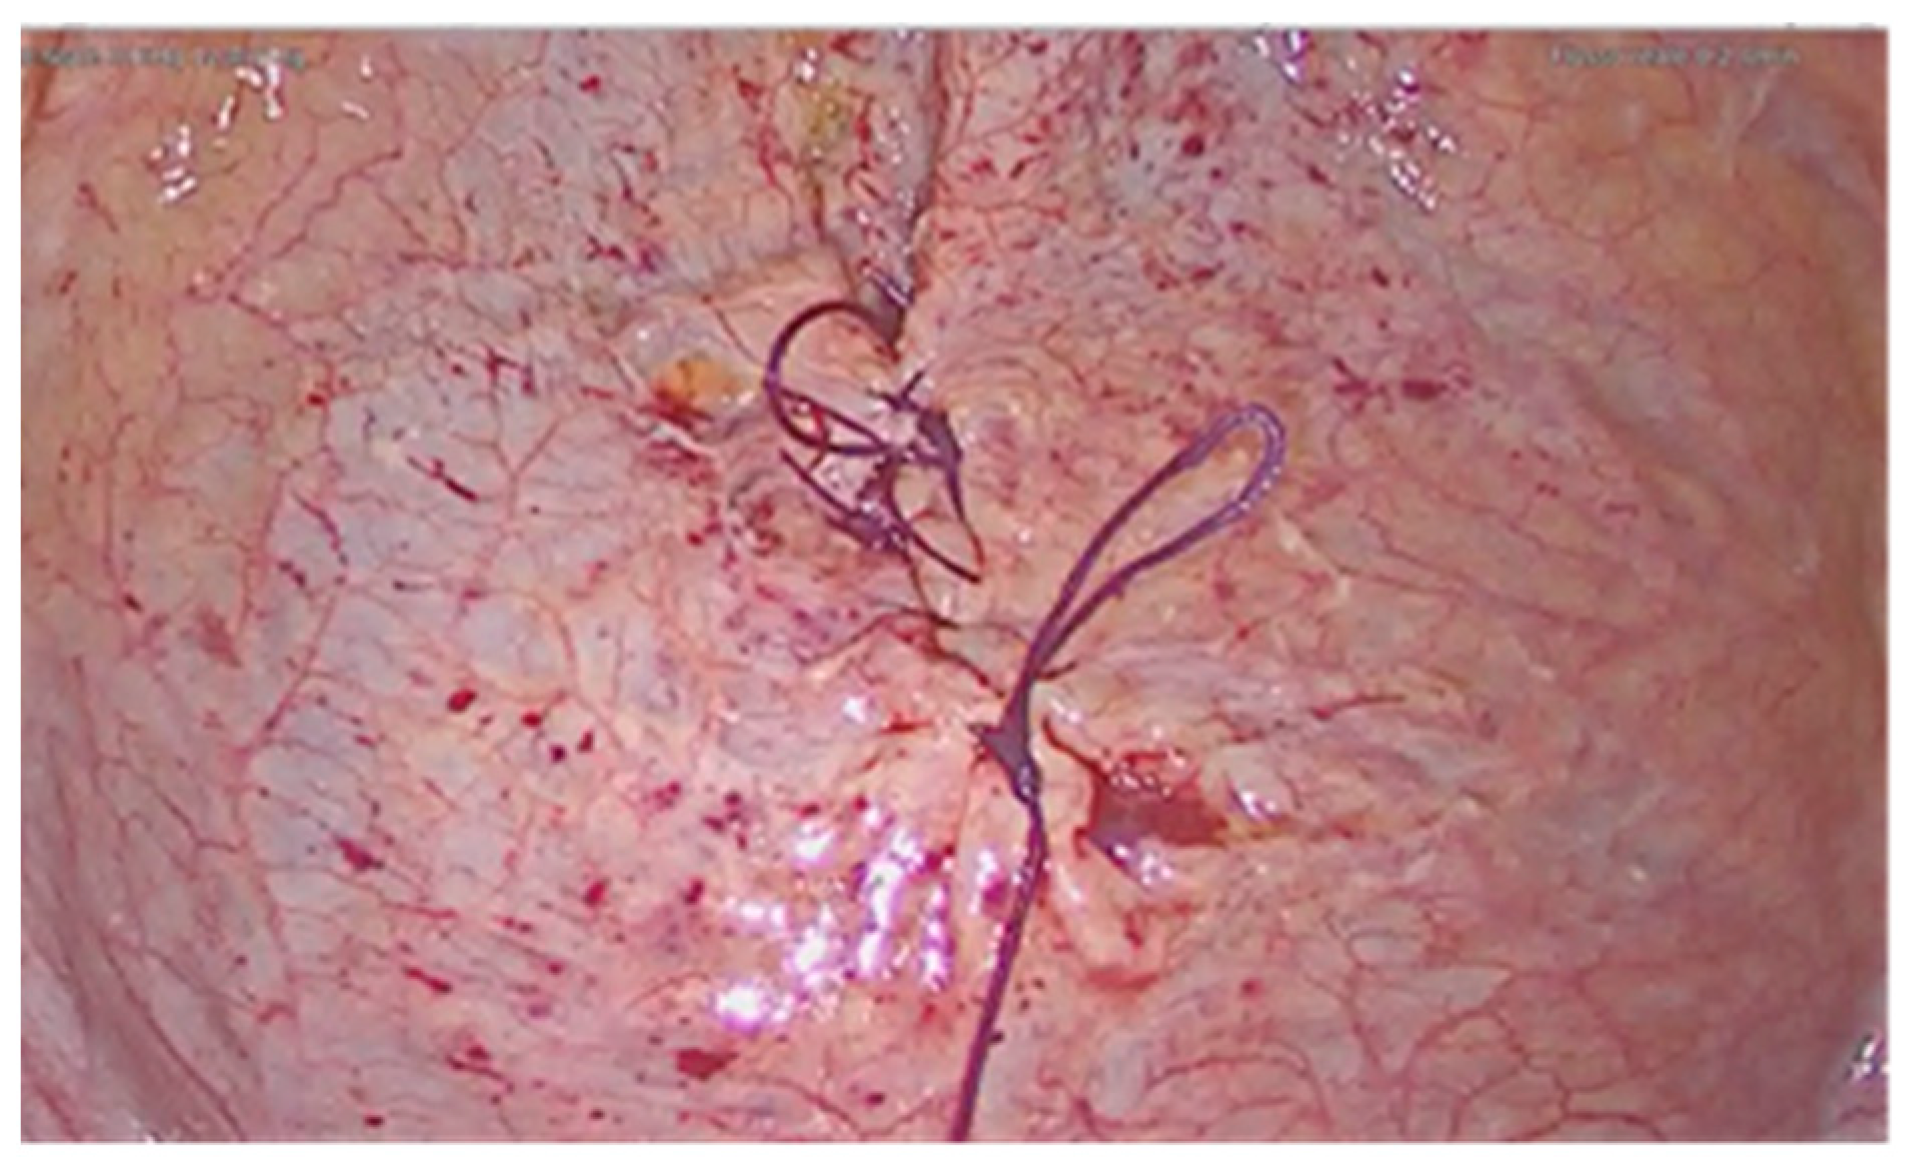

2. Case